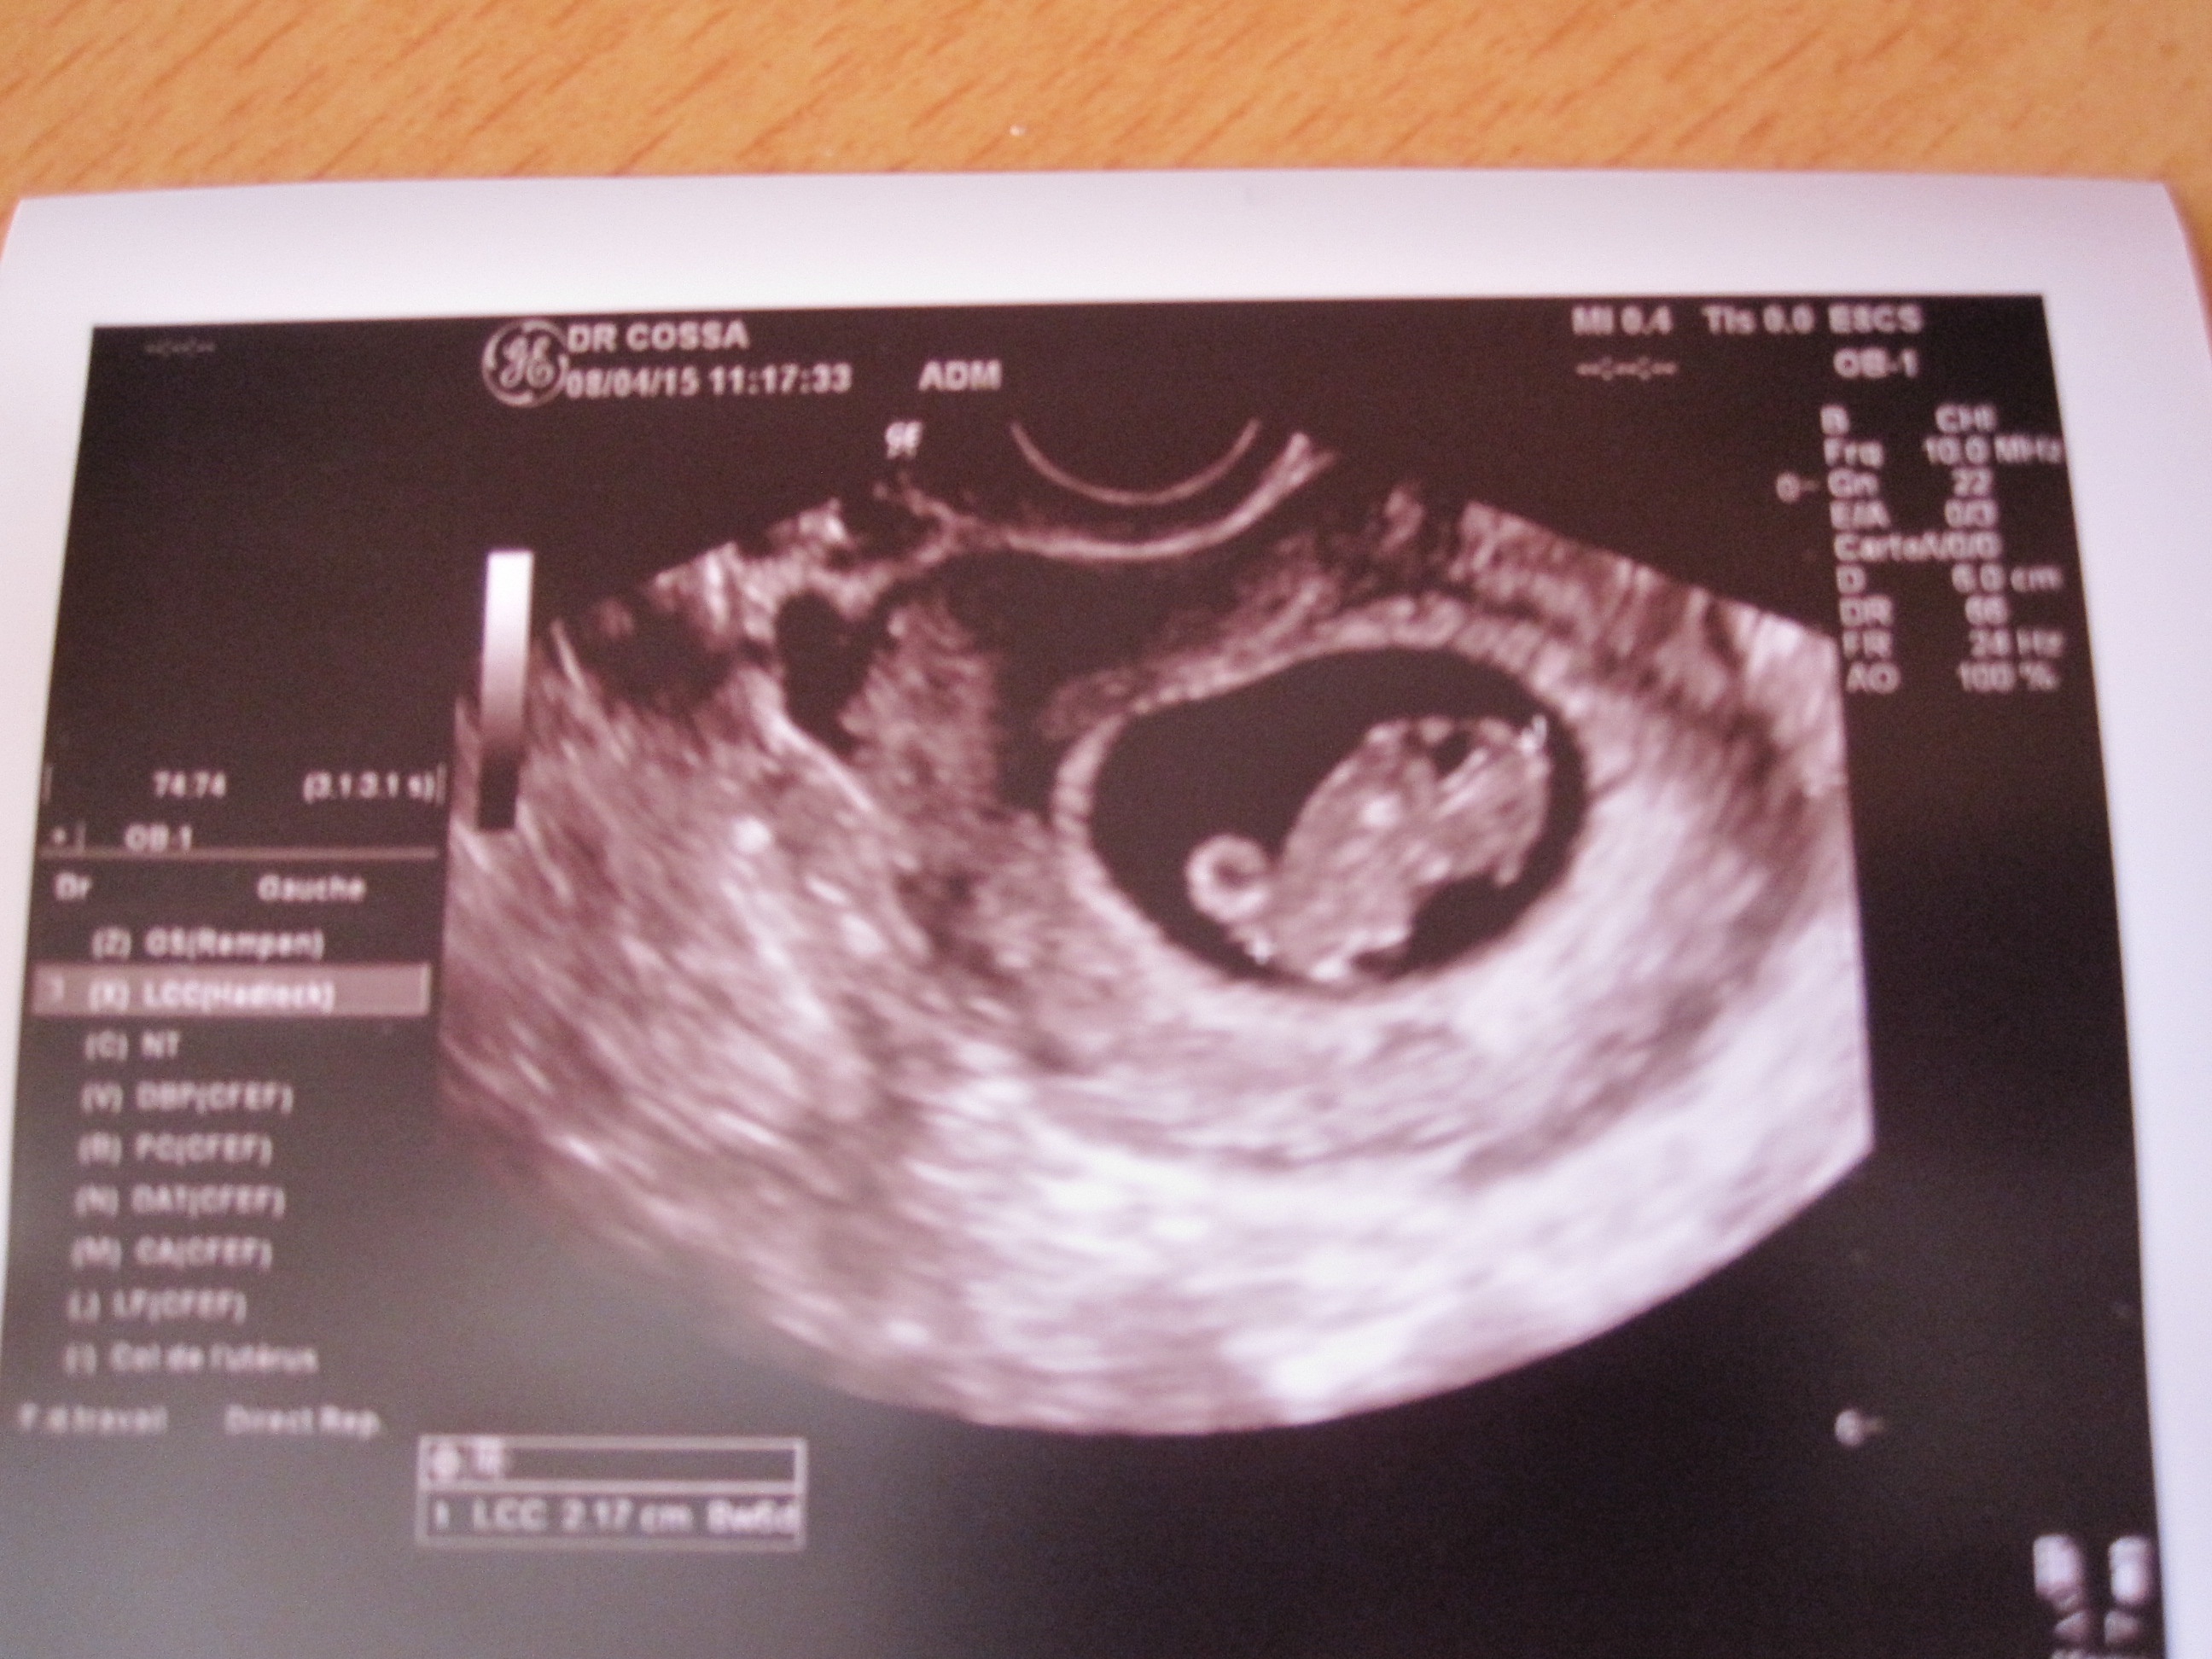

c'est super tu doit être trop contente d'avoir vu ta crevette ! Je pensais que ta DPA était avant moi !anna21130 a dit:echo nikel bébé fait 2,21cm son petit cœur ba la chamade prochaine echo le 28 avril avec declaration de grossesse

Ça va merci en arrêt cette semaine alors repos repos repos !Ti-miss a dit:ça va et toi ? J'ai eu mon écho pour les douleurs au ventre et tout va bien ça serai juste l'utérus qui tire. j'ai vu la crevette juste trop mignon elle fait 2.3 cm. quand j'ai entendu le cœur ça ma rassuré instantanément =)